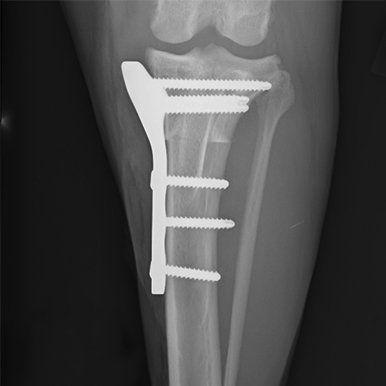

Tibial Plateau Leveling Osteotomy

This course is designed for veterinarians who want to specialize in orthopedic surgery and want to learn advanced techniques for managing knee injuries in small animals.